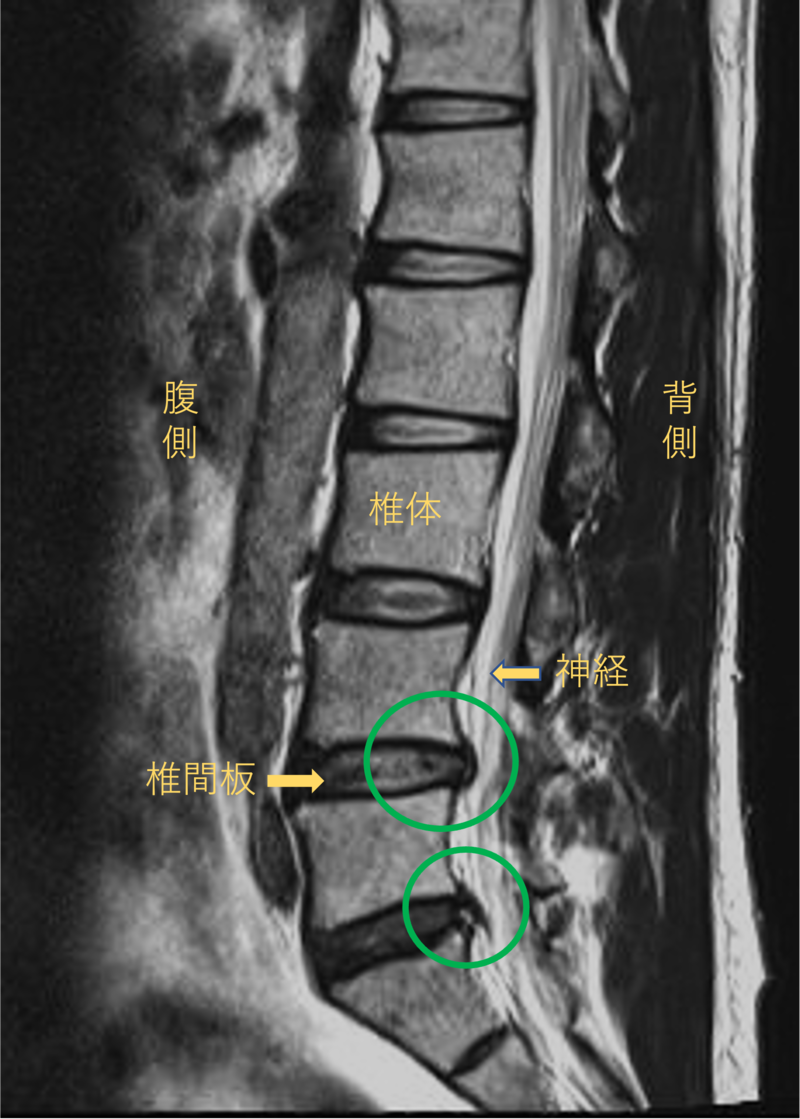

腰を横から見たMRI画像です。

腰椎という骨と骨の間に椎間板と呼ばれるクッションがあります。

このクッションの中身が飛び出す状態が椎間板ヘルニアと呼ばれます。

このMRI画像では、椎間板が背中側に飛び出して足に向かう神経が圧迫されることが痛み、しびれの原因となっておりました。